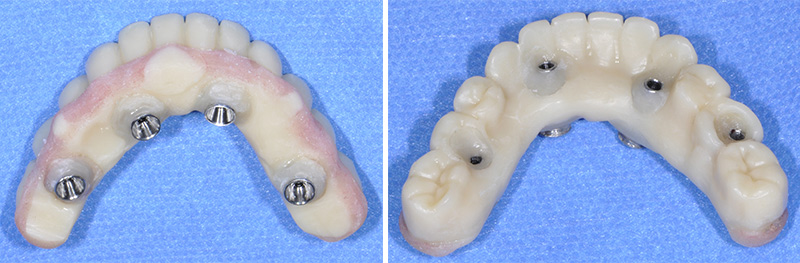

Fig. 49 : pour montrer la précision des ajustages, les guides sont imprimés par le laboratoire Giraud tandis que la restauration provisoire est conçue et usinés par Createch.

Les piliers prothétiques sont immédiatement vissés dans les implants sans déposer le guide de résection osseuse ; des gaines temporaires en titane sont transvissées sur les piliers et la restauration transitoire empilée sur le guide de résection, pour être solidarisée en bouche avec une colle composite. La finition très simple est réalisée au fauteuil et le patient quitte le cabinet dès la fin de la chirurgie avec sa restauration provisoire.

Fig. 55 et 56 : restauration provisoire terminée.